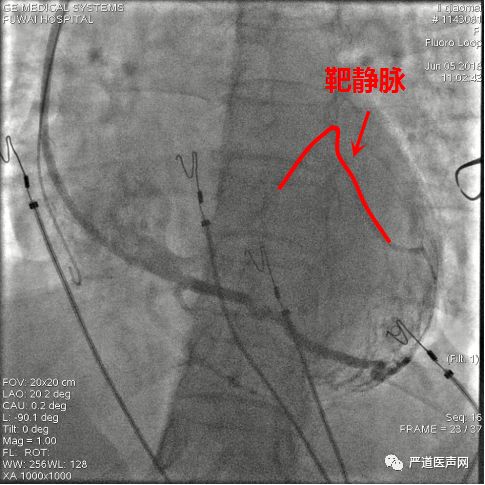

鞘中鞘经泥鳅导丝,通过瓣膜部位

鞘中鞘搭在靶静脉口

经鞘中鞘送左室导线进入侧静脉,张力大,左室导线前行困难

鞘中鞘前行支撑下仍无法进入

将鞘中鞘被再次送到靶静脉口支撑,由于分支太细,左室导线仍无法深入

调整左室导线,进入另一位置较高的分支

再次尝试PTCA导丝进入较高分支,左室导线顺利进入